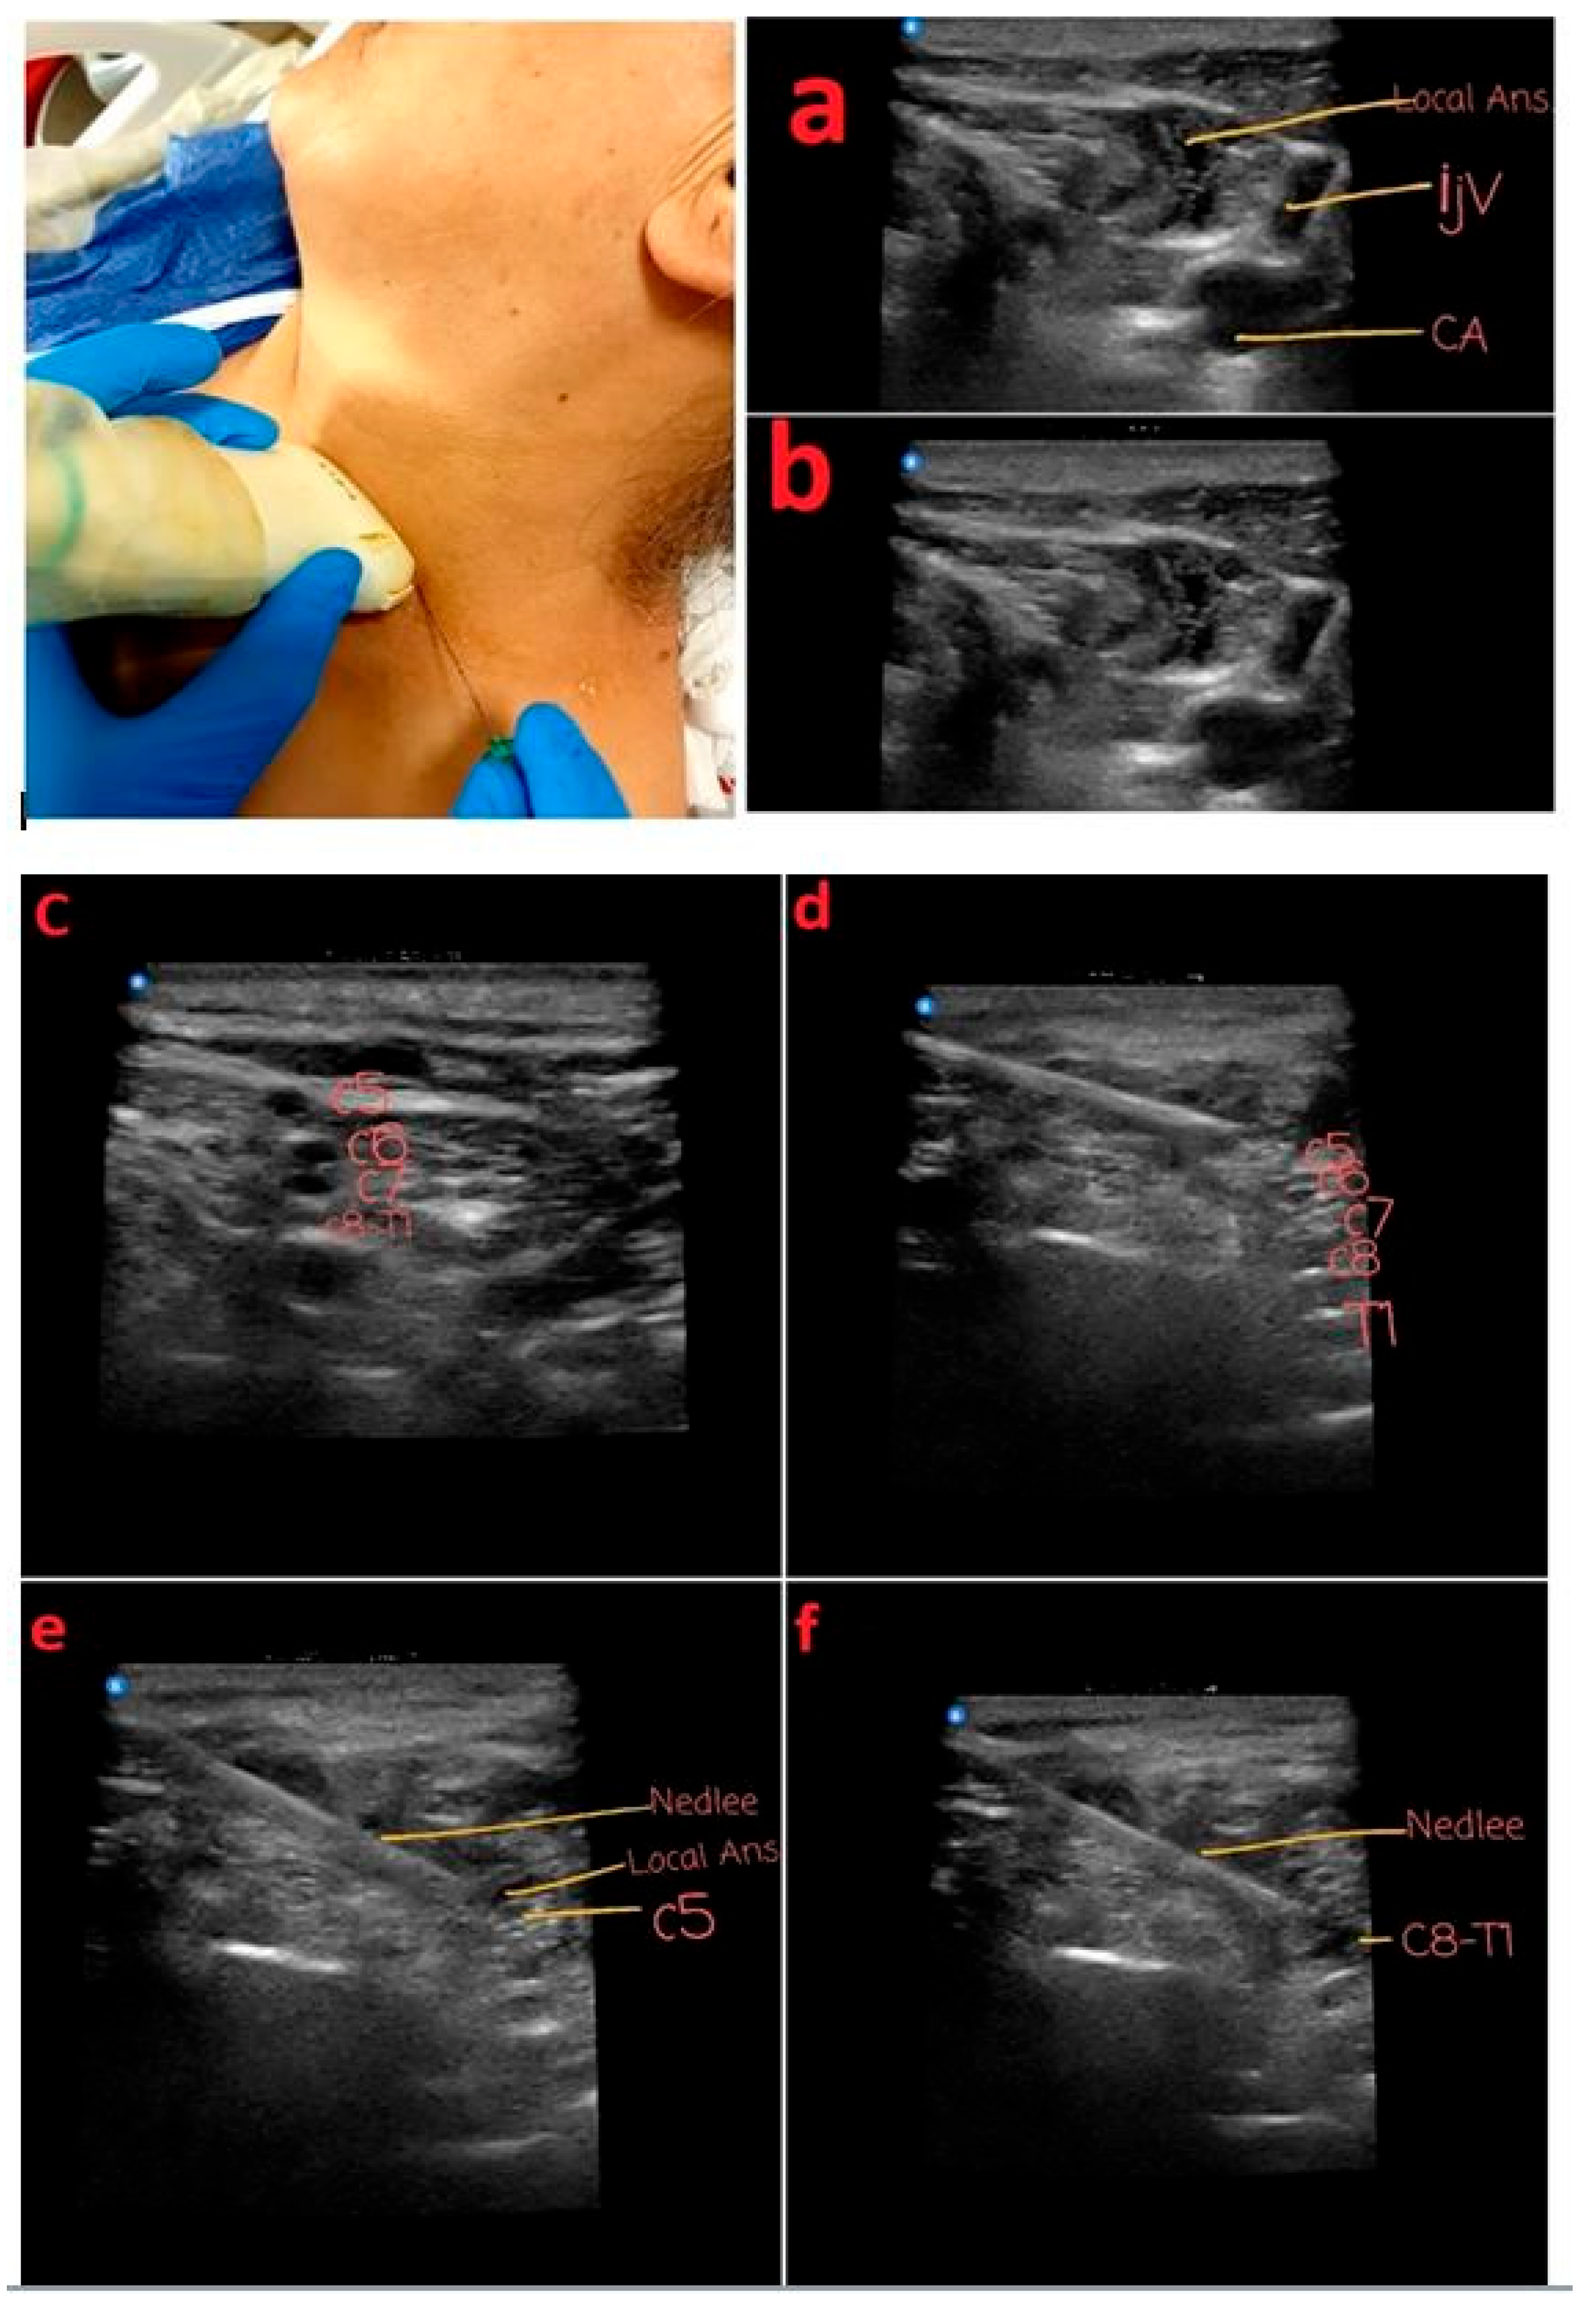

4. Anesthesia Preparation

4.1. Fluoroscopic-Guided Vascular Puncture in Posterior–Anterior (PA) Projection